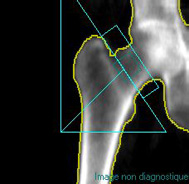

Deux sites sont analysés, le rachis

lombaire et le col fémoral Un système informatique analyse l’absorption

des Rayons X par le squelette et en déduit la densité minérale osseuse

(DMO). Celle-ci est comparée à celle de femmes du même âge (Z score)

et de trente ans (T score). C’est la diminution sensible du T score qui

permettra d’affirmer l’installation de l’ostéoporose. |